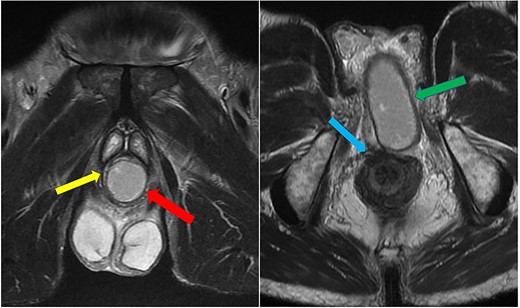

Imaging was suggestive of an infected Cowper’s syringocele. As the patient was clinically stable, a trial of antibiotic therapy was suggested. Repeat MRI a week later showed that the collection had extended into the corpus spongiosum, which now appeared expanded with the fluid density signal (Fig. 1). On a review, the urethral catheter was thought to be impairing potential drainage of the collection. It was removed, and a suprapubic catheter was inserted. Ultrasound guided aspiration failed to drain a significant amount of pus, which also grew S. anginosus. There was also radiological suspicion of a colovesical fistula. The patient was reviewed by the colorectal surgeons, who felt that as there were no other symptoms relating to the fistula, and the patient was physiologically frail, and defunctioning of the bowel would be inappropriate. Likewise, the patient was deemed too frail for any surgical management of the collection. He was discharged after a total of 6 weeks’ antibiotics. Repeat MRI 4 months later (Fig. 2) showed a smaller but persistent collection.

Case 1: sagittal and coronal T2-weighted images showing the collection (blue arrow) inferior to the prostate, and involving the corpus spongiosum (yellow arrow).